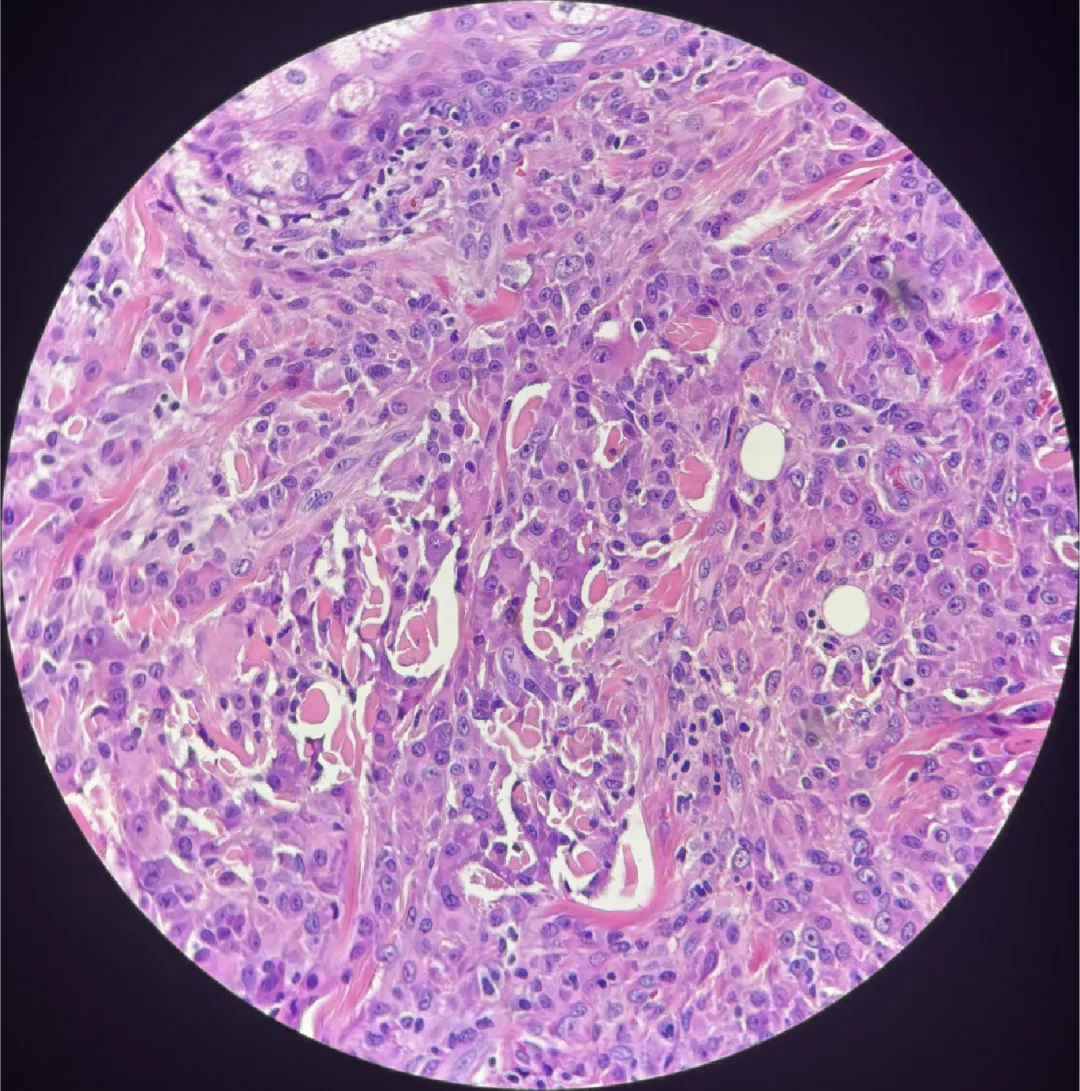

图2

Touton巨细胞即杜顿巨细胞其实就是多核巨细胞,不过它排列的更规则,更好看,排列成花环状或者马蹄形的多核巨细胞就叫Touton巨细胞

图1可见大量的组织细胞,Touton 巨细胞较少;

图2可见明显的Touton 巨细胞;可见一定程度的纤维化表现。